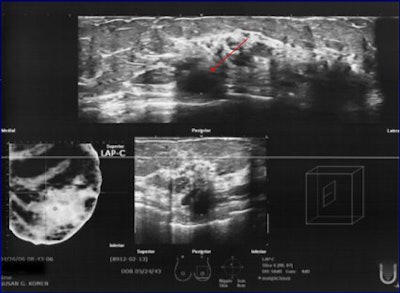

| Same patient as above. Second left breast cancer at 10 o'clock, 2 cm from the nipple was found on ABUS (and not seen on initial hand-held ultrasound exam), which corresponded to the posterior mass demonstrated mammographically and on breast MRI. Images courtesy of Dr. Jessica Guingrich. |